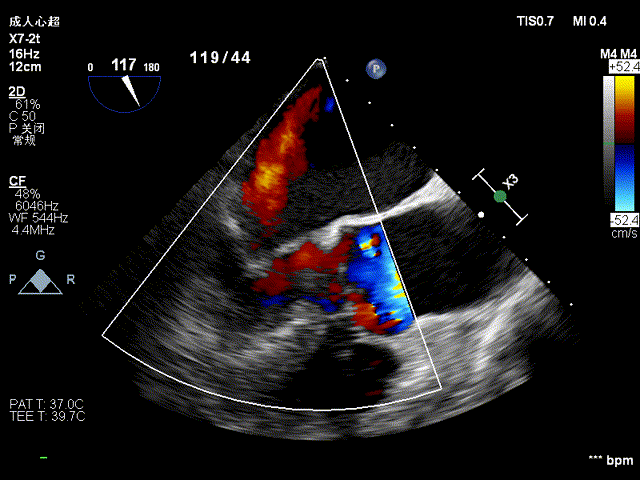

复查超声显示主动脉瓣架深度合适、位置稳定,瓣叶启闭正常,未见明显瓣周反流:

二尖瓣反流较术前显著减少: